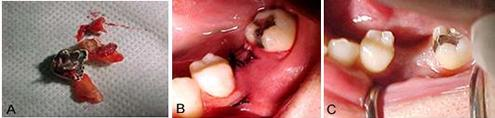

Figuras 2 a, b e c.

Figura 2a, mostra a cavidade óssea após a remoção do dente, evidenciando a grande perda óssea na área.

Figura 2 b, mostra o material de preenchimento que foi utilizado, Hidroxiapatita (Gen-phos) mais osso cortical e medular liofilizado (Gen-tech, Genius da Baumer), misturado com Colagel.

Figura 2 c, mostra o alvéolo refeito com material de reenchimento, onde será colocada uma membrana Intra-lock, para sutura dos retalhos.

Figuras 3 a, b e c.

Figura 3a, Raízes extraídas com o núcleo.

Figura 3b, sutura da ferida cirúrgica, procurando deixar a membrana reabsorvível bem fixada e os retalhos unidos de forma a propiciar uma cicatrização em primeira intenção, da mucosa gengival.

Figura 3c, a cicatrização da ferida cirúrgica, 30 dias após a extração e ROG.